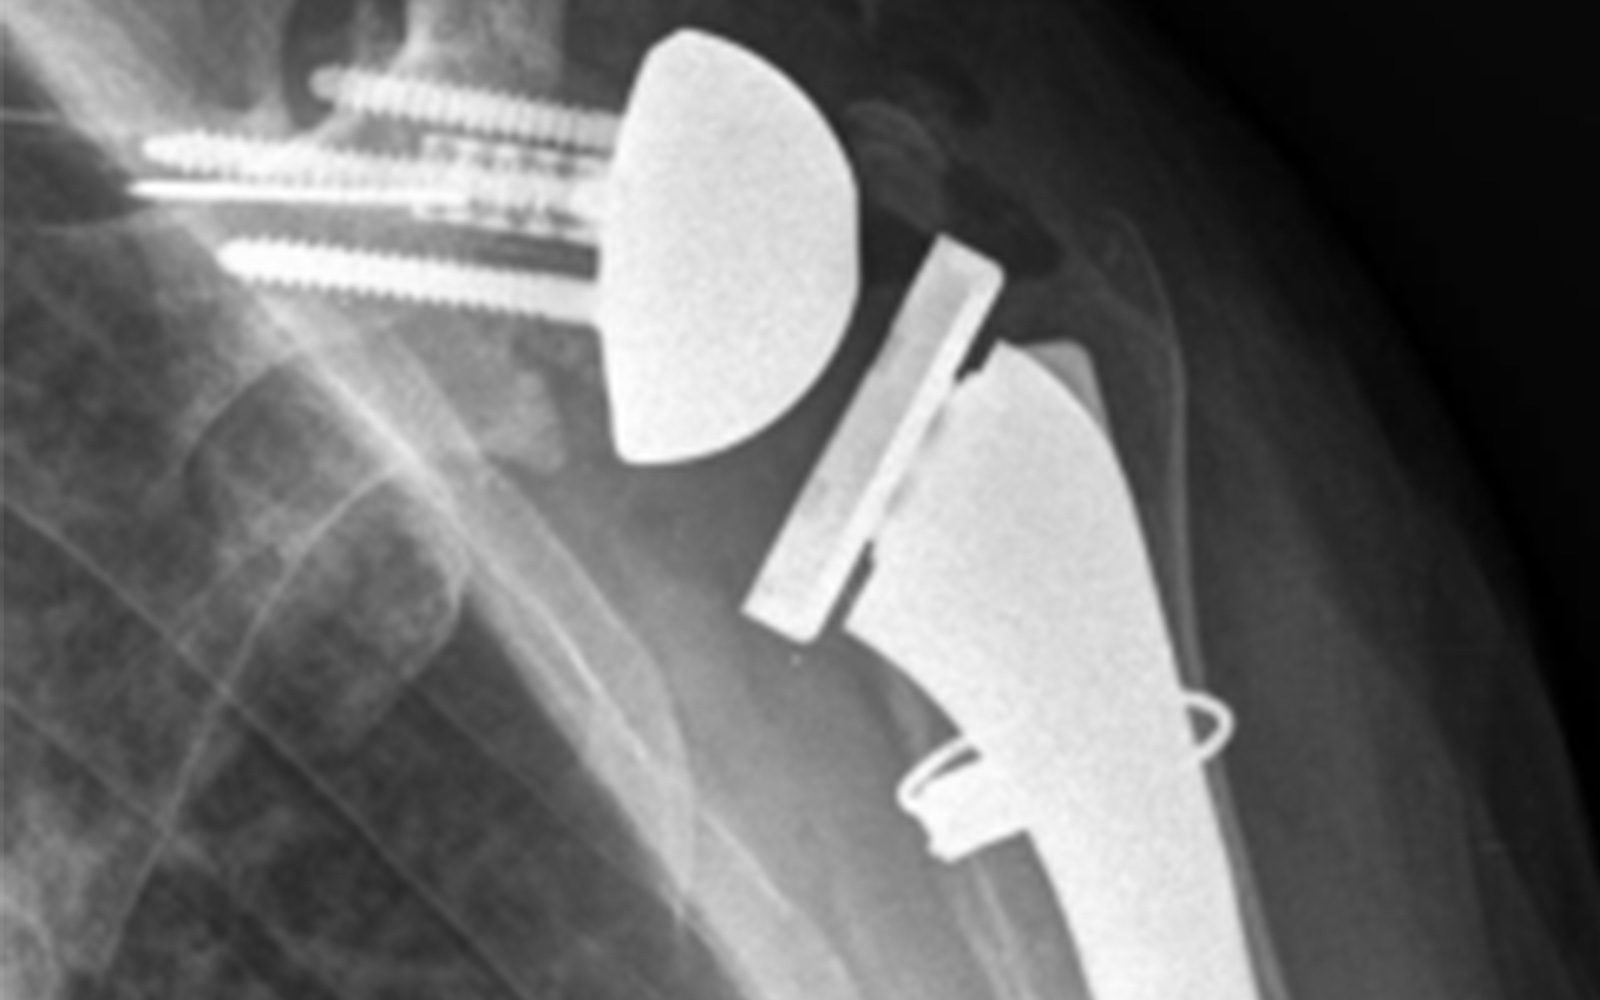

What is the Best Option for Addressing Difficult Glenoids With Implants?

Patient-Specific Guides With a Custom Implant: Is This a Practical Solution?